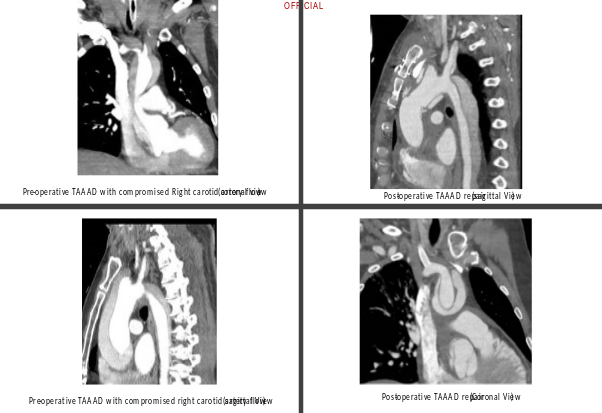

A sixty-four-year-old man presented to the emergency department with a history of syncope followed by tonic-clonic seizures and dense left hemiplegia, without chest or back pain. Because of low GCS, urgent intubation was required. Five years earlier, the patient had undergone an abdominal aortic aneurysm repair, and he had been under annual surveillance for a 45 mm ascending aortic aneurysm. On a head and neck CT with a brain perfusion scan, a significant right MCA area and right frontal lobe infarct without hemorrhagic changes were visible along with evidence of ATAAD affecting the aortic arch and its branches (Figure 2). On the gated CT aortogram, an extensive ATAAD involving arch vessels was visible from the ascending aorta to the abdominal aorta (Figure 1). Both true and false lumens supplied blood to the brachiocephalic artery, and the right common carotid artery's flow was compromised.

The multidisciplinary team's immediate suggestions included percutaneous fenestration and transluminal angioplasty of the right common carotid artery, followed by an MR perfusion scan to reassess cerebral circulation. Through the right common femoral artery, a successful percutaneous fenestration procedure into the right common carotid artery was carried out, and a stent was successfully deployed (Figure 3).

The patient experienced hemodynamic instability during MR imaging, necessitating an urgent pericardiocentesis, followed by prompt ATAAD central aortic repair with right femoro-femoral cardiopulmonary bypass. An antegrade cerebral perfusion via the brachiocephalic artery and hypothermic circulatory arrest at 24°C were used during the surgical procedure. By using the open distal approach, a supracoronary ascending aorta replacement and aortic valve resuspension procedure were performed. Recovery after surgery was difficult because of the patient's prolonged ventilation and acute kidney injury, which resolved within seven days. The patient was discharged home from stroke rehabilitation on postoperative day eighteen after full recovery from left hemiplegia.